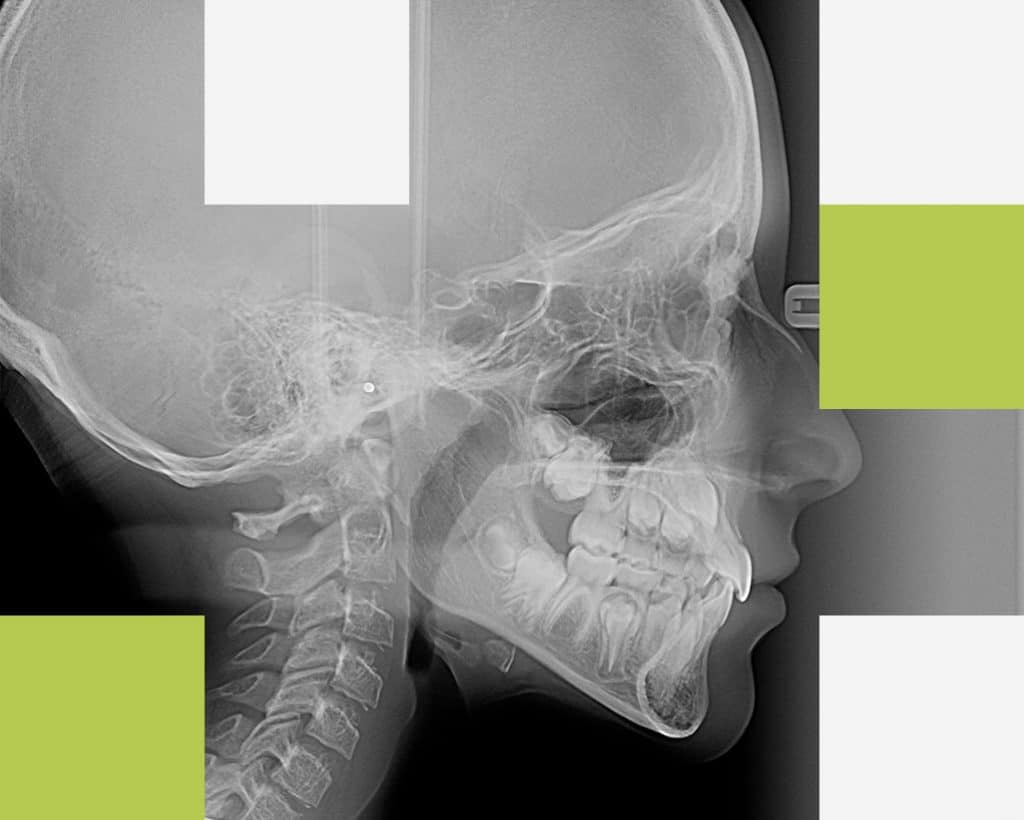

5. Teleradiografia de profil

Teleradiografia de profil este indicată atunci când se dorește aplicarea unui aparat ortodontic (pentru corectarea poziției dinților) sau corectarea profilului osos și a mușcăturii pacientului. Această radiografie evidențiază raportul dinților cu maxilarele și a maxilarelor cu oasele craniului pe care medicul ortodont le măsoară pentru a putea stabili diagnosticul și planul de tratament.